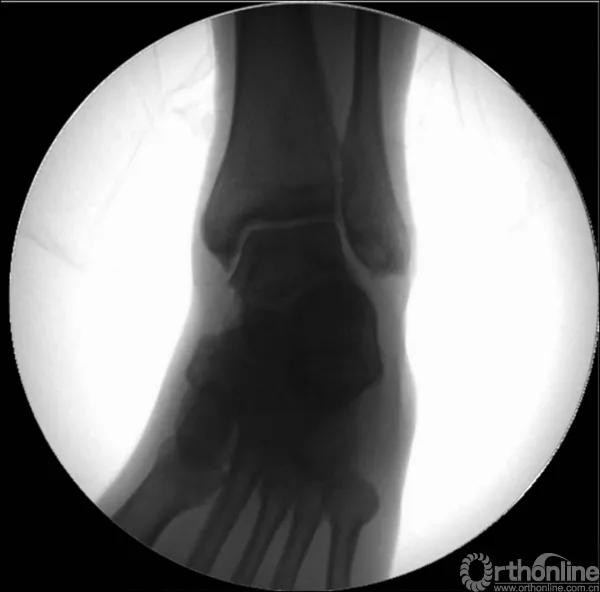

X线诊断:标准的踝关节影像学评估应包括3个位相:前后位(图5),踝穴位(内旋15°)(图6),侧位(图7)。

当踝关节严重损伤时内外踝及距骨将发生不同程度的移位(图8)。有时外踝骨折会伴有三角韧带的损伤,静态的X线摄片并不能准确地反映踝关节的稳定性,应力位片及MRI检查可完善对踝关节稳定性及韧带损伤的评估(图9)。此时应通过患肢损伤机制及放射资料准确判断踝关节损伤的类型以正确指导复位和固定。有时单纯内踝骨折可能是更为复杂的“Maisonneuve骨折”的一部分,该骨折还包括腓骨近端骨折及韧带联合损伤,故X线检查应投照整个胫腓骨。

图9 应力位X线片(三角韧带断裂)